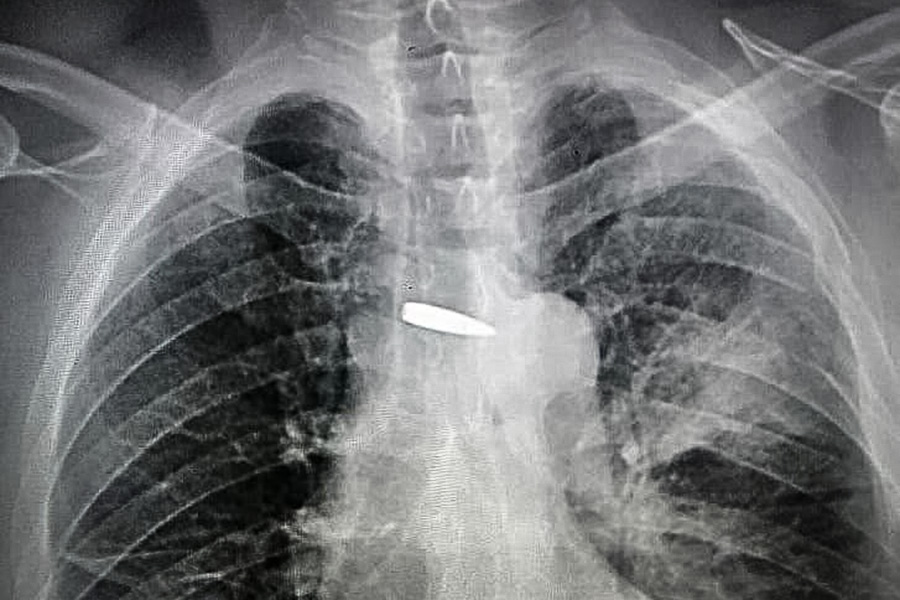

У лютому 2023 року Вікторович отримав поранення на бойовому завданні. Захисник відчув гострий пекучий біль у ділянці серця та виділення крові з кашлем. Куля пройшла крізь ліве плече, ліве легке і буквально за міліметри від серця, а потім роздробила поперечний відросток п'ятого грудного хребця.

Він був госпіталізований й лікарі Хмельницької міської лікарні вилучили кулю, яка могла забрати життя Вікторовича. Потім медики подарували її герою на день народження.

Кулю знайшли у серця. Військовий із Покровська повернувся на фронт після тяжкого поранення: зворушлива історіяЛікарі виявили кулю у серця Віталія (фото: ngu.gov.ua)